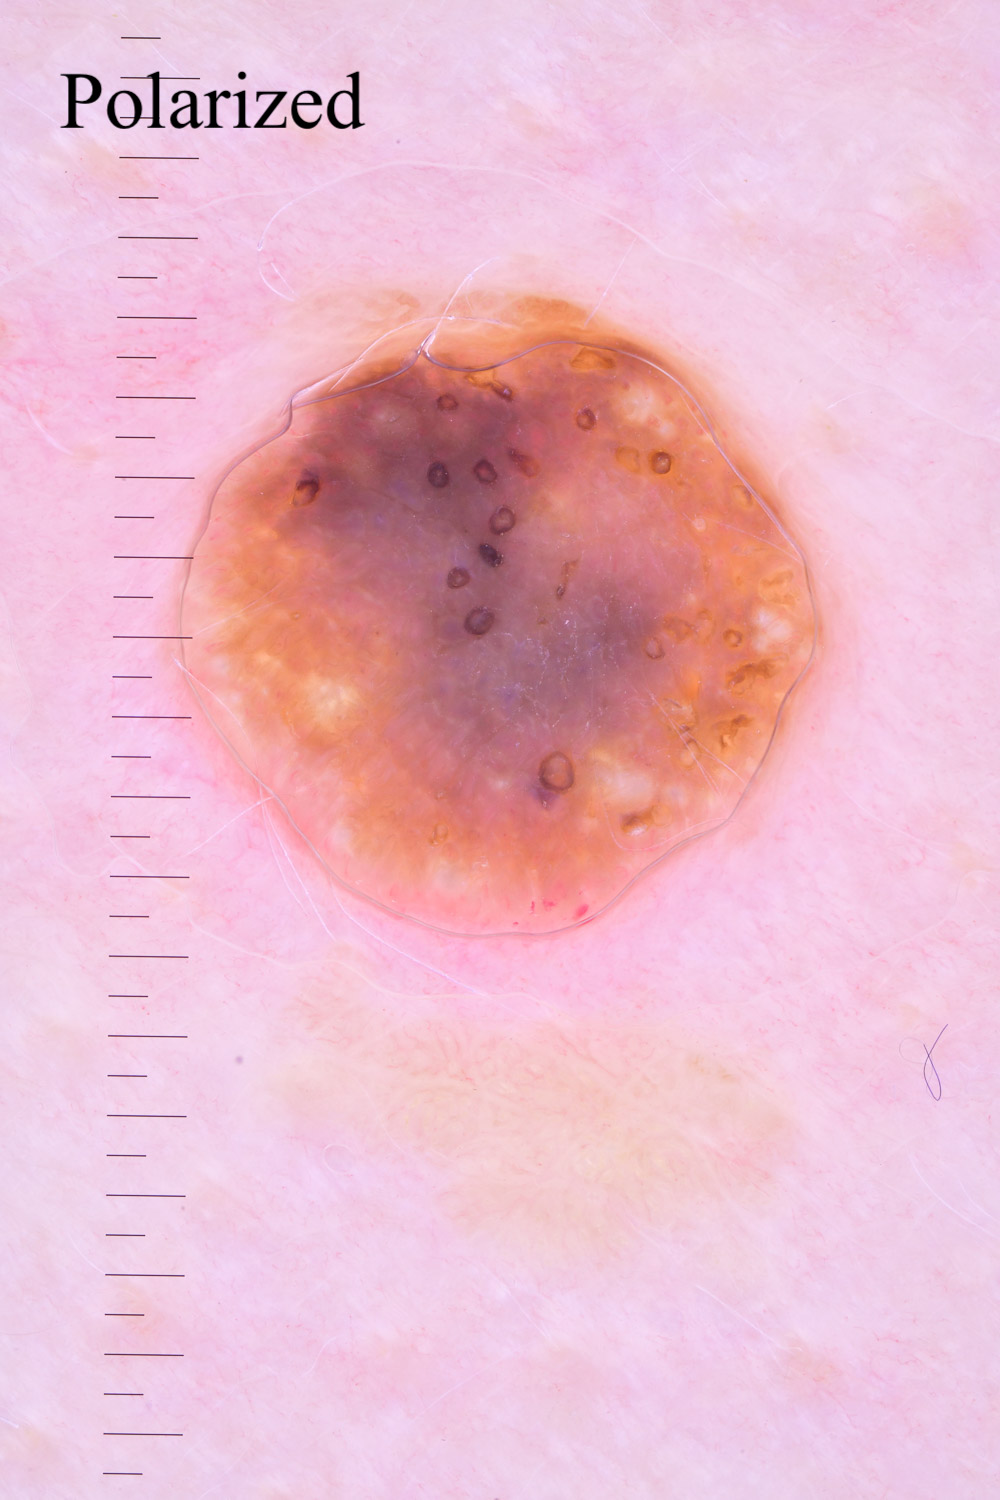

Case: 157